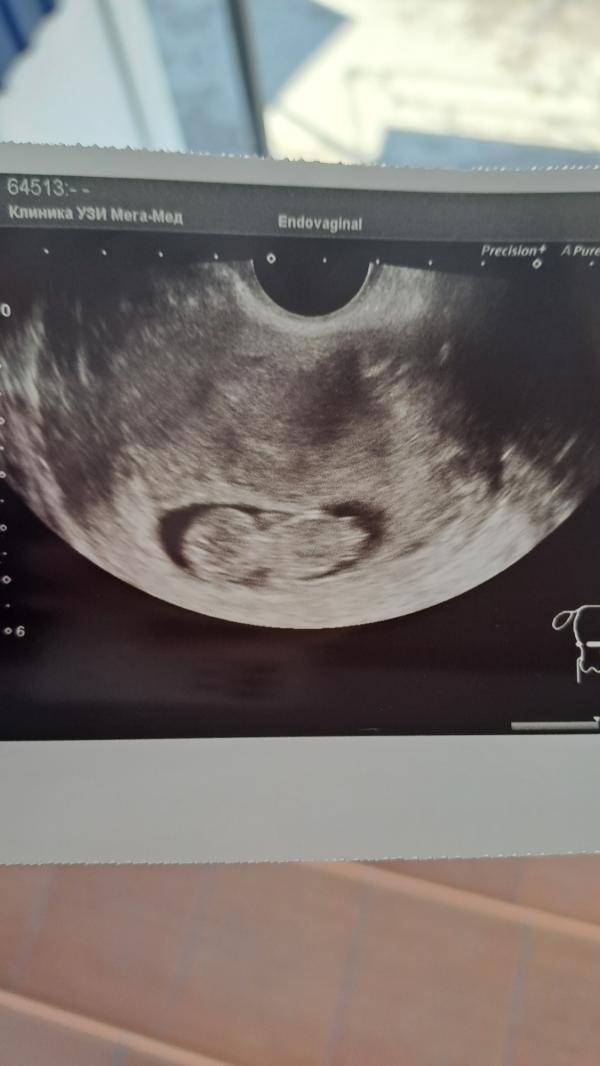

Нам 10 недель ❤️ креветочка моя

Впервые была на таком отличном УЗИ.

Показали всё, рассказали: вот позвоночник, вот полушария мозга, желудочки головного мозга, нервная система, животик, ножки, ручки, все хорошо, без патологий. Я даже удивилась, что на таком сроке настолько все видно 🥹

Активный очень, фоткаться не хотел(а) 🥰